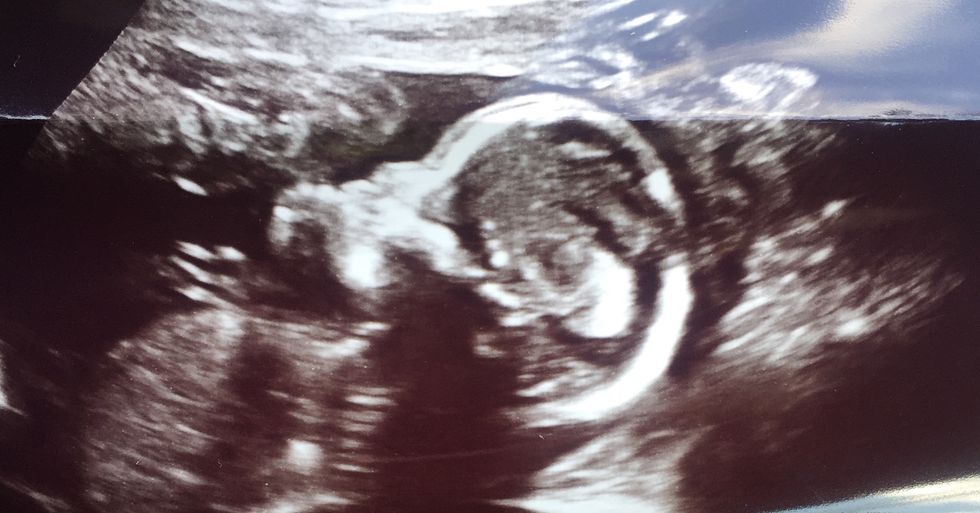

June 21st, 2017 is a day to remember FOREVER! I was just 21 weeks pregnant. I never had a thought in my mind that I’ll be going into labor that day. My fiancé & I just found out that we were having a baby boy two weeks prior.

Baby boy was able to stay in the room with us. Our angel was perfect. He had ALL of his features. 10 fingers, 10 toes, perfect little ears & nose. Not to mention he looked just like his daddy. I held him the whole time. Just crying & staring at him. He was perfect. I just couldn’t understand why.